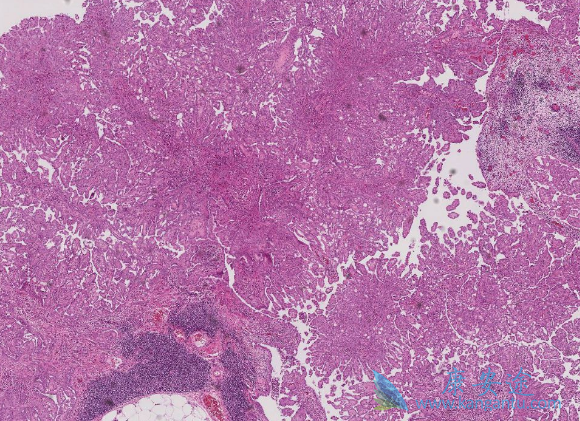

间皮瘤是一种罕见的恶性肿瘤,主要是由接触石棉引起。在美国,每年超过2000人被诊断为间皮瘤,而且确诊时大都为晚期。目前对于间皮瘤的治疗还没有标准疗法,医生只能根据每位患者的具体情况治疗治疗方法。虽然如此,此类患者的预后很差,一般术后中位生存期也大约在1年左右。也因此被称为恶性间皮瘤

恶性间皮瘤

恶性间皮瘤有哪些症状?在早期,60%~90%的患者出现呼吸困难、胸痛、干咳和气短,约10.2%病人可以有发热及全身不舒服等症状,3.2%病人以关节痛为主诉症状。到了中晚期,50&-60%的患者表现为大量胸腔积液,其中血性胸腔积液占3/4。晚期患者表现为衰弱、恶病质、腹腔积液以及胸腹部畸形。临床表现是肿瘤进行性侵袭而未受到有效控制的结果。